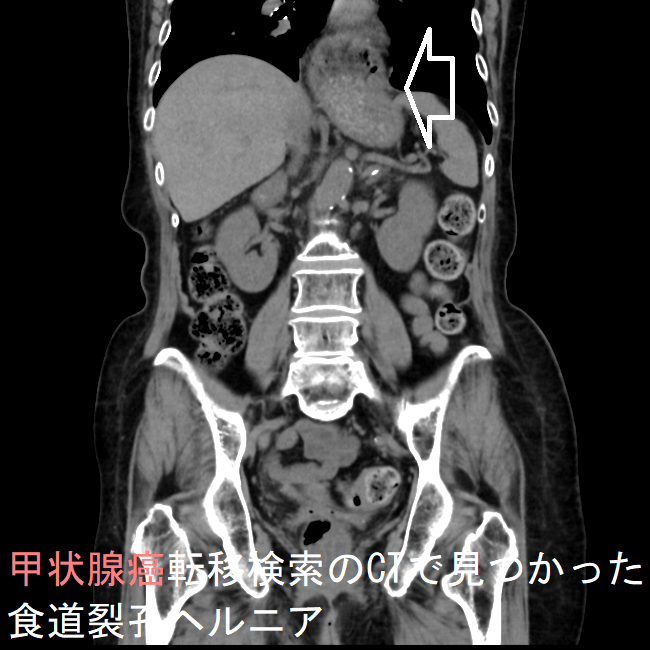

甲状腺癌転移検索のCTで見つかった僧帽弁狭窄症(MS) 食道裂孔ヘルニア(水平断)